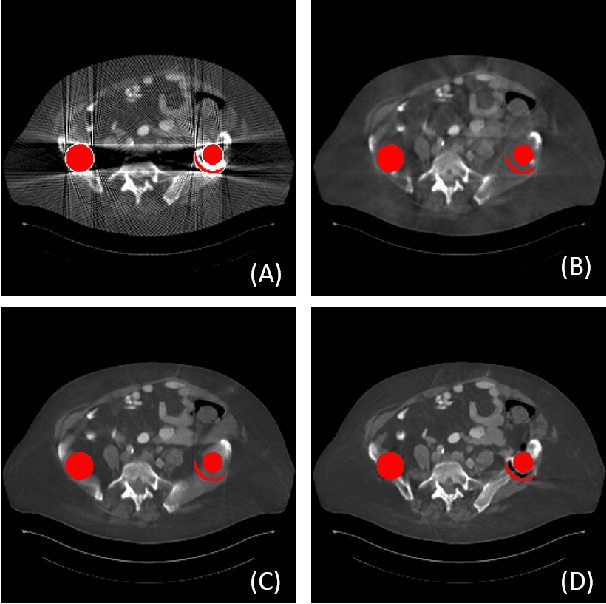

Abstract:Due to the presence of metallic implants, the imaging quality of computed tomography (CT) would be heavily degraded. With the rapid development of deep learning, several network models have been proposed for metal artifact reduction (MAR). Since the dual-domain MAR methods can leverage the hybrid information from both sinogram and image domains, they have significantly improved the performance compared to single-domain methods. However,current dual-domain methods usually operate on both domains in a specific order, which implicitly imposes a certain priority prior into MAR and may ignore the latent information interaction between both domains. To address this problem, in this paper, we propose a novel interactive dualdomain parallel network for CT MAR, dubbed as IDOLNet. Different from existing dual-domain methods, the proposed IDOL-Net is composed of two modules. The disentanglement module is utilized to generate high-quality prior sinogram and image as the complementary inputs. The follow-up refinement module consists of two parallel and interactive branches that simultaneously operate on image and sinogram domain, fully exploiting the latent information interaction between both domains. The simulated and clinical results demonstrate that the proposed IDOL-Net outperforms several state-of-the-art models in both qualitative and quantitative aspects.

Abstract:Metal implants can heavily attenuate X-rays in computed tomography (CT) scans, leading to severe artifacts in reconstructed images, which significantly jeopardize image quality and negatively impact subsequent diagnoses and treatment planning. With the rapid development of deep learning in the field of medical imaging, several network models have been proposed for metal artifact reduction (MAR) in CT. Despite the encouraging results achieved by these methods, there is still much room to further improve performance. In this paper, a novel Dual-domain Adaptive-scaling Non-local network (DAN-Net) for MAR. We correct the corrupted sinogram using adaptive scaling first to preserve more tissue and bone details as a more informative input. Then, an end-to-end dual-domain network is adopted to successively process the sinogram and its corresponding reconstructed image generated by the analytical reconstruction layer. In addition, to better suppress the existing artifacts and restrain the potential secondary artifacts caused by inaccurate results of the sinogram-domain network, a novel residual sinogram learning strategy and nonlocal module are leveraged in the proposed network model. In the experiments, the proposed DAN-Net demonstrates performance competitive with several state-of-the-art MAR methods in both qualitative and quantitative aspects.